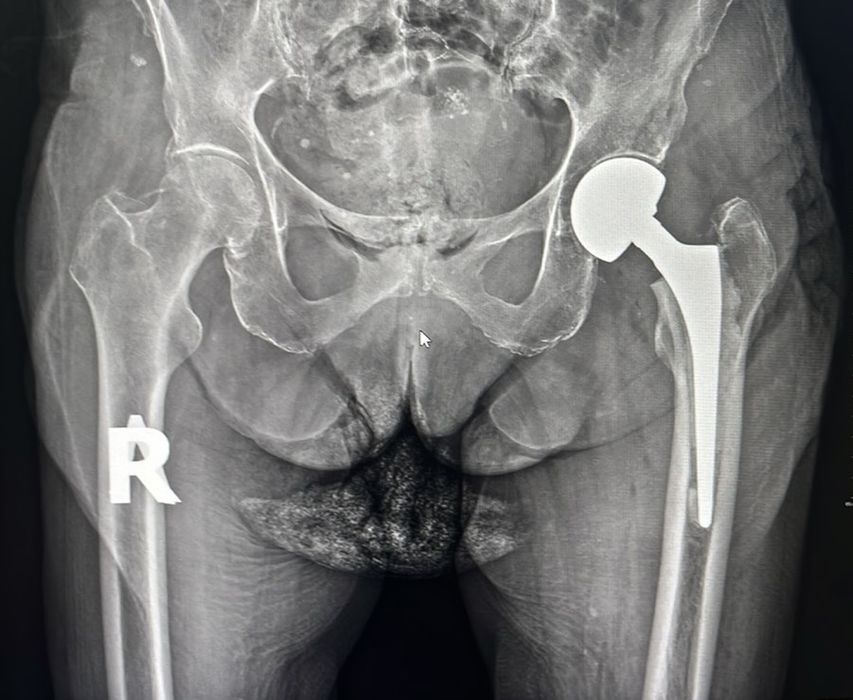

Перелом шийки стегна. Безкоштовне ендопротезування.

Лікар вищої категорії у Київській міській клінічній лікарні виконує імплантацію безкоштовного ендопротезу тазостегнового суглобу за Програмою державних медичних гарантій - виключно при переломі шийки стегна. Позачергово. Безкоштовно.